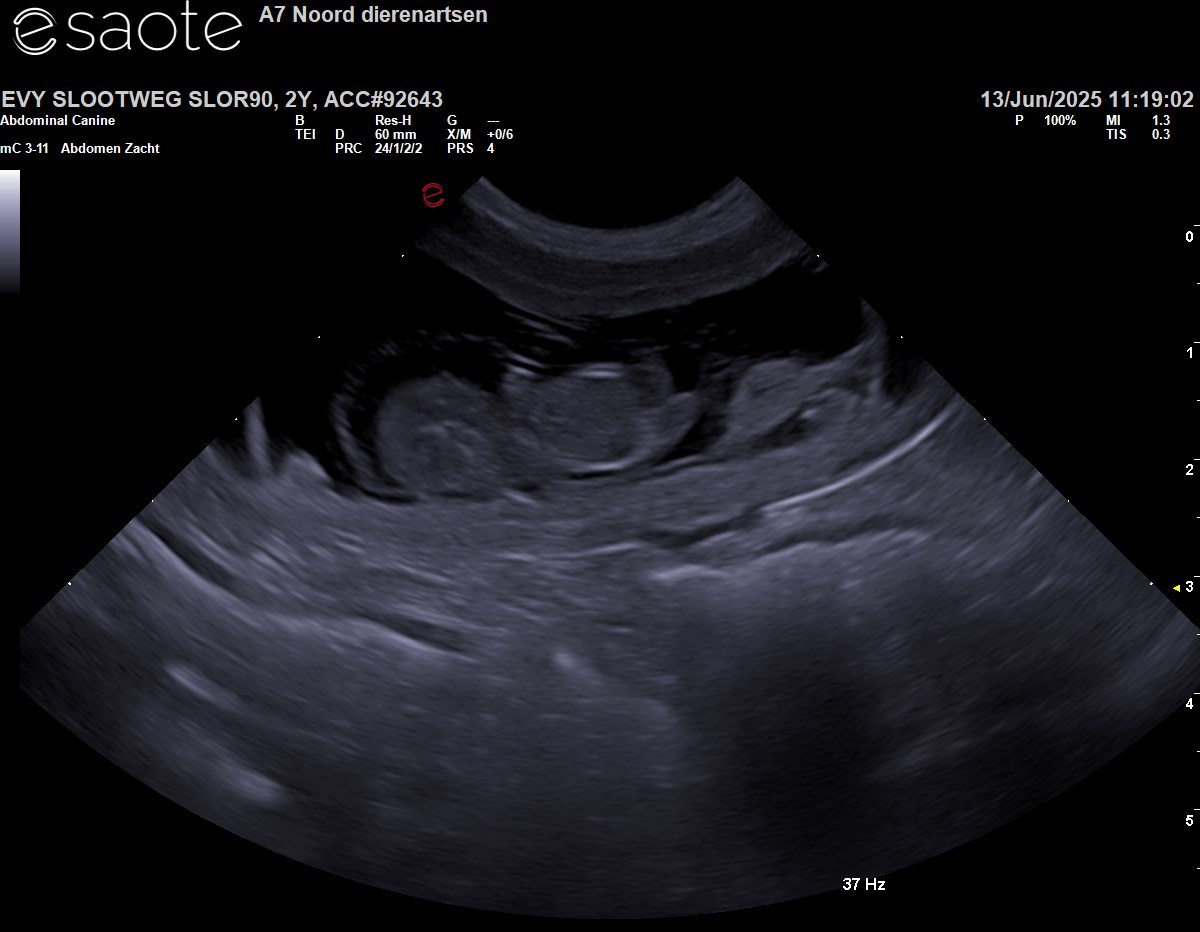

Vandaag zijn wij met Evy naar de dierenarts geweest voor een Echo en daarmee is bevestigd dat ze zwanger is. Hieronder de foto.